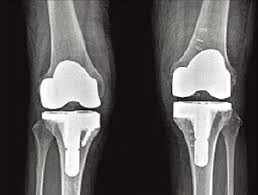

무릎 인공관절수술비용이 궁금하신가요? 퇴행성 관절염 등으로 무릎 인공관절 수술을 고려하는 분들이 많은데, 비용은 건강보험 여부, 병원급, 선택진료 옵션, 장비 사용(로봇) 등에 따라 크게 달라집니다. 국내 비용부터 의료관광 비용, 보험 적용 여부까지 자세히 알려드립니다.